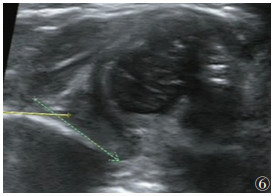

2.220例CMT合并DDH中,左侧DDH 8例,右侧DDH 6例,双侧DDH 6例。20例40髋中,Ⅰ型14髋(35.0%)(图 1)、Ⅱa型17髋(42.5%)(图 2)、Ⅱb型5髋(12.5%)(图 3)、Ⅱc型1髋(2.5%)(图 4)、Ⅲ型2髋(5.0%)(图 5)、Ⅳ型1髋(2.5%)(图 6)。

| 图 6 女,71 d,左髋α=30°,β无法测量,GrafⅣ型,骨顶缘扁平,软骨顶被脱位的股骨头推向下方 |

目前,超声已被认为是诊断CMT和DDH最敏感的工具之一,并被广泛用于两者的诊断[2, 13]。一方面,超声可用于量化CMT患儿肌肉纤维化程度,确定肿块的大小和位置,并指导临床制订治疗方案[17]。本组非肿块型98例,肿块型78例。非肿块型常仅表现为头歪向一侧,此时运用超声测量双侧的SCM的厚度、对比是否有局限性增厚,观察肌纤维排列、肌纹理回声及与周围组织关系从而早期诊断CMT;对于肿块型,超声可明确肿块来源,排除淋巴管瘤、淋巴结等其他颈部肿块。根据患侧SCM的声像图特点推测肌肉纤维化程度,从而选择治疗措施,并通过超声计算出SCM挛缩长度、确定临床手术方案和松解范围[1, 18-21]。此外,超声在后期疗效观察和判断预后上也有重要价值,通过测量治疗前后SCM厚度、肿块大小,以及观察病变区血流情况,有利于评估CMT疗效。另一方面,相对于体格检查较明显的CMT,DDH可能更易忽视;尤其6个月以内的婴幼儿,因髋臼软骨未骨化X线不能显像,早期诊断DDH更困难。而超声波可穿透软骨,清晰显示关节囊、关节盂唇、股骨头软骨及髋臼等解剖结构;其中Graf超声静态测量方法因敏感性高,且观察者间的图像采集测量解读差异小、可重复性较高等优点,能更早期发现DDH,在婴儿髋关节超声检查中最普及[16, 22-23]。本组176例CMT患儿,通过Graf方法对髋关节进行分型,显示并发DDH 20例(40髋),其中Ⅰ型14髋(35.0%)、Ⅱa型17髋(42.5%)、Ⅱb型5髋(12.5%)、Ⅱc型1髋(2.5%)、Ⅲ型2髋(5.0%)、Ⅳ型1髋(2.5%),临床上根据具体病理阶段选择和实施合适的治疗,病情均得到不同程度的改善、获得满意的治疗效果。此外,应用彩色多普勒超声还可监测DDH治疗过程中股骨头血供情况,以减少股骨头坏死的发生[24]。